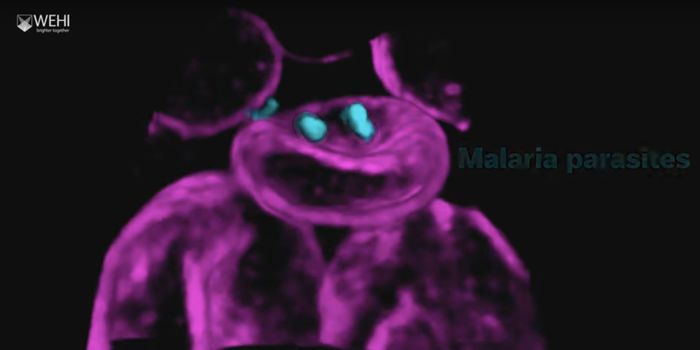

NOV 23, 2021MicrobiologyWhen the parasite Plasmodium falciparium is transmitted from mosquitoes to humans, it causes malaria. So what does it do ...

NOV 05, 2021MicrobiologyMalaria is the most common infectious disease in the world, and infected over 225 million people in 2019 according to th ...

FEB 04, 2021ImmunologyMalaria is a disease caused by single-celled parasites from the Plasmodium group, transmitted to humans through infected ...